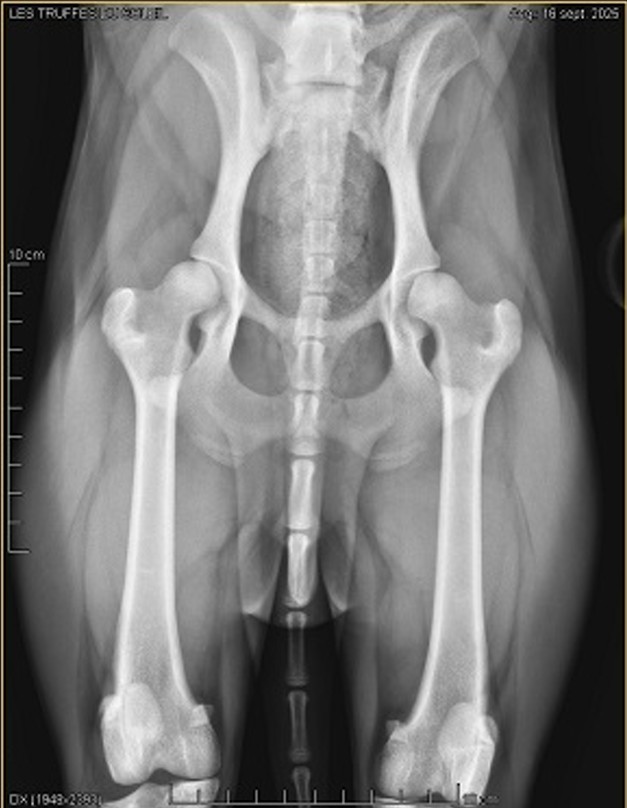

On discute également de ses hanches "affaissées" : on soupçonne chez Hercule un problème de dysplasie.

L'association décide de le faire venir en métropole pour confirmer sa dysplasie, et lui fournir les soins nécessaires.

Le 16 septembre, l'orthopédiste confirme sa légère dysplasie.

Une alimentation dédiée ainsi que des soins d'hydrothérapie lui sont prescrits.